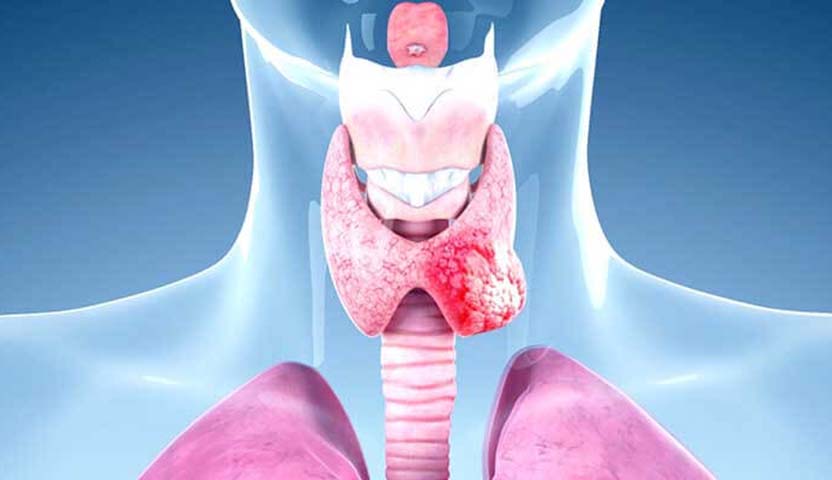

هل سرطان الغدة الدرقية الجريبي ينتشر؟

يمكن أن ينتشر سرطان الغدة الدرقية الجريبي وينتقل إلى أجزاء أخرى من الجسم، مثل الرئة، العظام، الدماغ، الكبد، المثانة والجلد في حال لم يتم علاجه مبكرًا، وبشكل عام من الصعب علاج السرطان المنتشر.